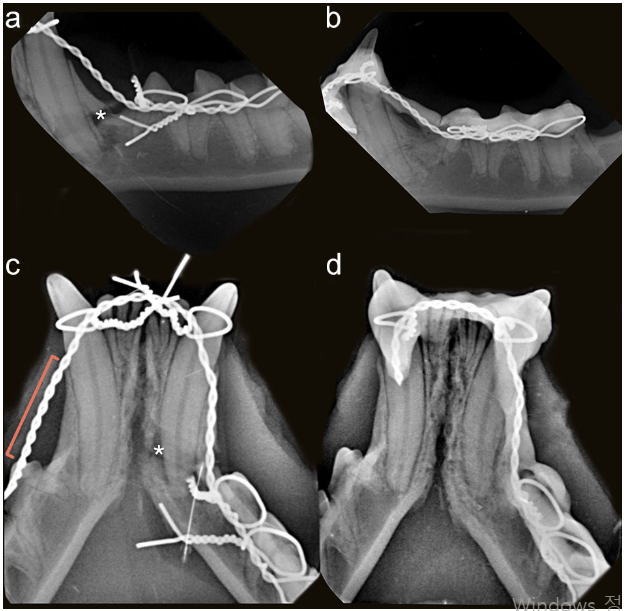

WRICS는 치아를 지지대 삼아 와이어와 치과용 복합 레진(치아 색깔의 단단한 재료)으로 골절된 뼈 조각들을 고정하는 비침습적 방법이다. 주로 개의 하악골 골절 치료에 효과적인 것으로 알려졌으나, 고양이에 대한 연구는 상대적으로 부족했다. 본 연구는 2004년부터 2024년까지 21년간 두 곳의 대학 동물병원(펜실베이니아 대학교 부속 동물병원 및 리스본 수의과대학)에서 WRICS로 하악골 몸통 골절 치료를 받은 고양이 12마리(총 13개 골절)의 의료 기록을 후향적으로 분석하였다. 분석 대상은 송곳니 또는 그 뒤쪽 부위 골절 사례로 한정했으며, 골절 유형, 부목의 형태와 범위, 치유 기간, 동반된 치아 손상, 치료 관련 합병증 등을 조사하였다. 골절은 주로 송곳니와 세 번째 작은어금니 사이에서 가장 빈번하게 발생했으며(61.5%), 대부분 단순 골절(84.6%)이면서 수직적인 힘에 저항하기 어려운 불리한 형태(unfavorable, 69.2%)였다.

연구 결과, WRICS를 이용한 하악골 몸통 골절의 평균 치유 기간은 약 50일(49.8 ± 13.9일)로 나타났다. 이는 기존에 보고된 평균 10주(약 70일)보다 단축된 결과이다. 부목 제거 시 모든 사례에서 골절 부위의 안정성이 확인되었고, 방사선 사진상 뼈가 생성되어 골절 틈을 메우는 소견(가골 형성)이 관찰되었다. 일부 사례에서는 부목 제거 시점에도 방사선 사진상 골절선이 희미하게 관찰되었으나(53.8%), 이는 치유 과정의 일부로 판단되었으며, 치유 기간 자체에는 통계적으로 유의미한 차이를 보이지 않았다. 특히, 골절선 내 치아 손상에 대한 치료(발치, 신경치료 등) 유무가 뼈 치유 기간에 영향을 미치지 않는다는 점도 주목할 만하다. 이는 WRICS가 치아 손상이 동반된 복잡한 경우에도 효과적인 안정성을 제공함을 시사한다. 흥미롭게도, 전통적으로 골절 부위 양쪽으로 최소 2개 이상의 치아를 부목에 포함해야 안정성을 확보할 수 있다고 여겨졌으나, 본 연구의 3례에서는 골절선 뒤쪽으로 단 하나의 치아만 부목에 포함되었음에도 성공적인 치유가 관찰되었다. 이는 수술 후 저작력 감소나 행동 변화 등 다른 요인들과 더불어 WRICS 자체가 고양이에서 충분한 안정성을 제공할 수 있음을 보여준다.